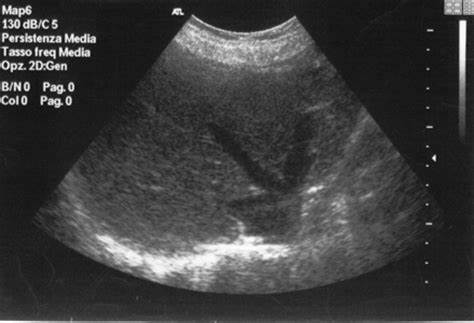

1. 肝臟B超:B超可對肝硬化、脾腫大、肝結(jié)石、脂肪肝、肝癌等做出診斷。而且安全性好、無過敏反應(yīng),檢查費用相對較低。適合普通人群常規(guī)檢查。